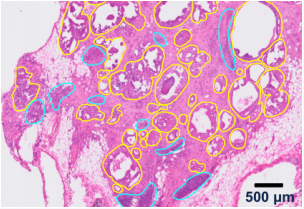

这份 FFPE 人类乳腺导管原位癌样本的 Visium HD 分析构建了 一张无偏的全转录组图谱,并鉴定出肿瘤微环境中的主要 细胞类型和状态。

| 带有癌症区域(黄色)和免疫富集区域

(青色)的病理学注释的 H & E 染色结果

▲定位组织驻留细胞群,包括免疫细胞或癌细胞,以发现它们的相互作用以及对疾病或治疗应答的贡献。

Visium HD 数据是以 2 µm 以及多种拼接尺寸输出的。上图中的数据是在 8 µm 下可视化的。